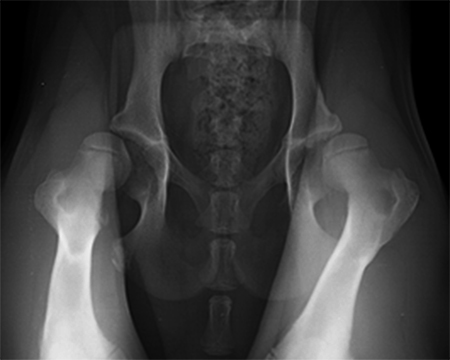

A 5-month-old spayed female labrador retriever puppy weighing 22.0 kg presented with bilateral hind limb weakness and a bunny-hopping gait in the hind limbs. Physical examination revealed bilateral hip instability (positive Ortolani sign) and mild pain on full extension of the hips. Slight crepitus was palpated in the left hip. The gluteal muscles appeared to have mild atrophy. The neurological exam was normal. Radiographic examinations revealed bilateral hip subluxation and a distraction index of 0.5 of the right hip and 0.7 of the left hip (Fig 3). No evidence of osteoarthritis was observed.